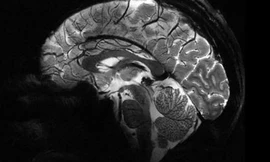

TPO - Chụp cộng hưởng từ (CHT hay MRI) là một kỹ thuật ghi hình ảnh sử dụng từ trường mạnh và sóng radio để tạo nên những hình ảnh của các cơ quan và cấu trúc bên trong cơ thể. MRI không sử dụng phóng xạ ion hóa (không dùng tia X)

Những triển vọng được mở ra bởi cỗ máy độc đáo này trên thế giới là rất lớn, giúp các nhà khoa học thiết lập các chẩn đoán tốt hơn cho nhiều loại bệnh về não.

TPO - Được 13 bác sĩ tại Mỹ chăm sóc trong vòng 1 năm và qua 24 lần kiểm tra điều trị nhưng chứng đau đầu của Natasha không giảm. Cô qua đời vì u não do không được chụp cộng hưởng từ (MRI).